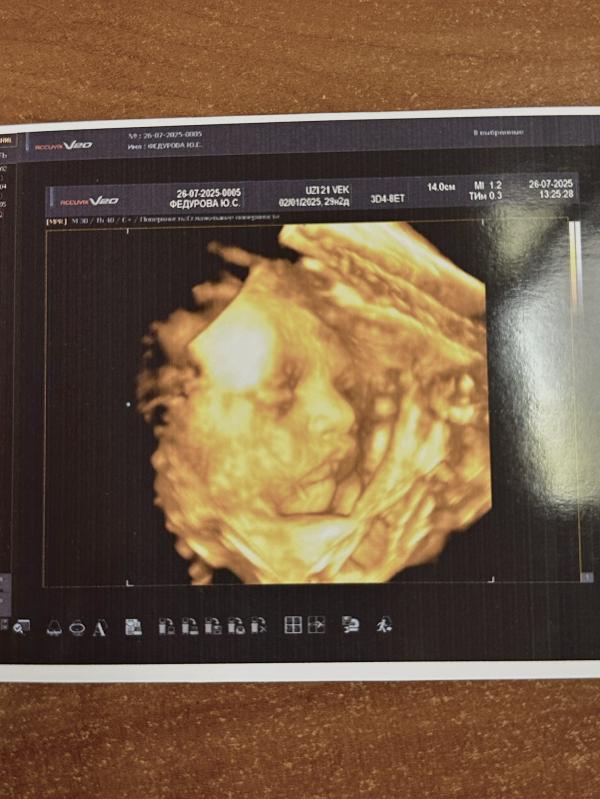

девочки!!! я в восторге

выбрали в итоге Узи 21век на Ольховой

далеко от нас, но цена приятная - 1700

мы выбрали с записью видео на флешку, это 2400

делала на сроке 28нед по скринингу

теперь не могу насмотреться

Мы там УЗИ с младшей делали)) недорого и запись хорошая) первое фото - топчик